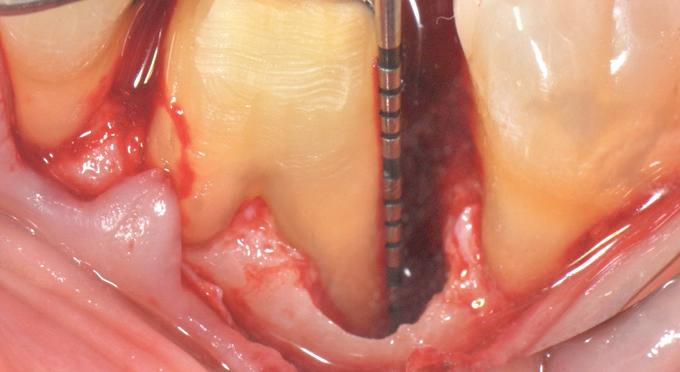

year old female patient presented with clinical and radiographic evidence of an mm.

The crown was biologically shaped and the root detoxified using Ellman burs. After flap opening and complete defect debridement, GEM S® was used to fill the defect.

year old female patient presented with clinical and radiographic evidence of an mm

The goal of the procedure was to restore the lost hard tissue support ie. periodontal

to allow for a significantly improved longterm prognosis. The evidenced-based usage of GEM ® as part of our surgical protocol has been documented to do just that: hard and soft tissue regeneration in intrabony defects.

F l ap re fle c tio n sh o wing the d o n the dis t al o ≥ m m poc ket d epth